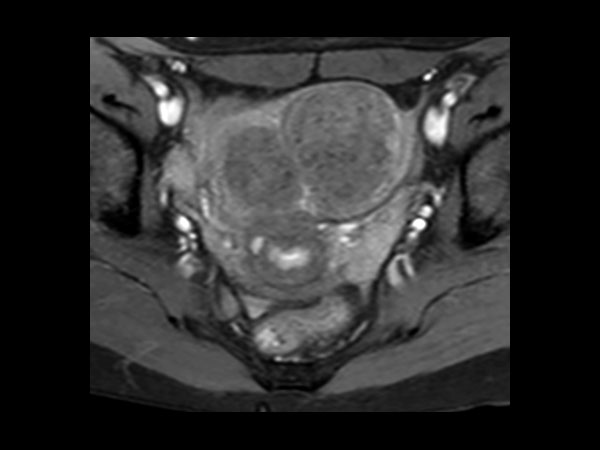

Female Pelvis

Toyonaka Hospital, Japan